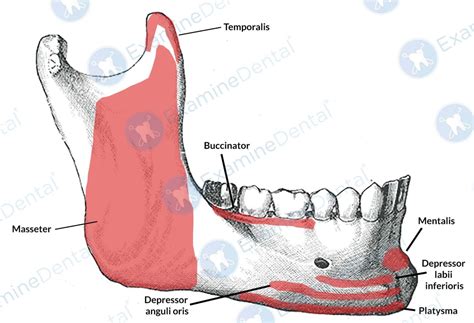

The coronoid process in mandible is a triangular, flattened structure that extends upward from the ramus of the mandible. It is situated anterior to the condylar process and is separated from it by the mandibular notch. The coronoid process serves as a crucial attachment site for the temporalis muscle, which is responsible for elevating the mandible during chewing and closing the mouth. Additionally, the coronoid process provides attachment for the masseteric fascia and the buccinator muscle.

The primary function of the coronoid process in mandible is to serve as an attachment site for the temporalis muscle. This muscle is one of the primary muscles of mastication, responsible for the elevation of the mandible. When the temporalis muscle contracts, it pulls the coronoid process upward, closing the jaw. This action is essential for biting and chewing food, as well as for speaking and swallowing.

In addition to its role in mastication, the coronoid process in mandible also plays a part in the stability and movement of the temporomandibular joint (TMJ). The TMJ is a complex joint that connects the mandible to the temporal bone of the skull. The coronoid process, along with the condylar process, helps to guide the movement of the mandible during opening and closing, as well as during lateral and protrusive movements.